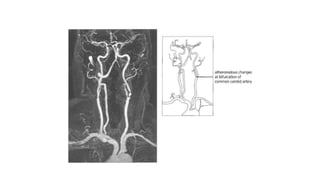

• a. Form large arteries as atheromatous lesion of the carotids.

• 1. Diseased (sclerotic) vessels in old age as in diabetes,

hypertension and arteriosclerosis